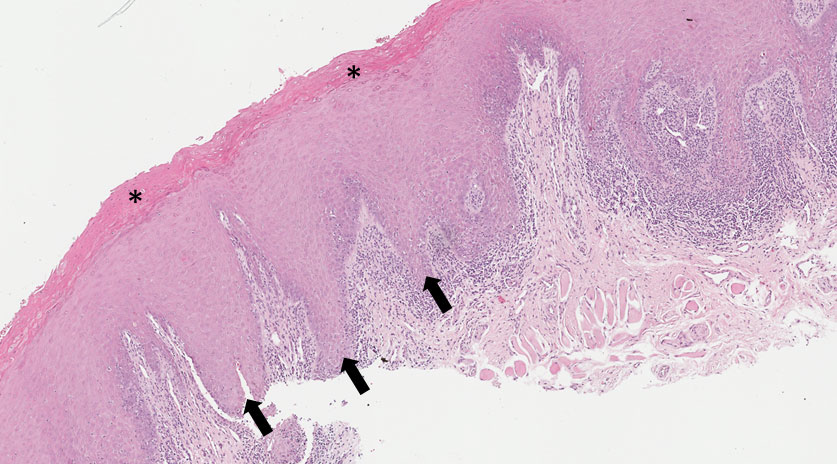

9.2 Granuloma piogênico

Descrição

Fragmento de mucosa bucal revestida parcialmente por tecido epitelial. Em área nota-se ulceração (exposição do tecido conjuntivo) e membrana fibropurulenta (Figuras 3, 4 e 5). No tecido conjuntivo subjacente evidencia-se intensa angiogênese e vasos congestos. Permeando os vasos observa-se infiltrado inflamatório crônico (linfócitos e plasmócitos) e fibras colágenas (Figuras 4, 5 e 6).

Dados importantes para o diagnóstico

Observar que a lesão é parcialmente revestida por tecido epitelial (Figuras 3 e 4) e em áreas há perda epitelial e o conjuntivo está exposto (Figuras 3 e 5). Na superfície nesta região observa-se membrana fibrinopurulenta (asterisco amarelo — Figura 5). No tecido conjuntivo nota-se inúmeros vasos de neoformação (com células ovaladas na periféria- Figura 5 setas e Figura 6 asteriscos) muitos congestos (cheios de hemácias) e infiltrado inflamatório crônico.

Figura 3

Figura 4

Figura 5

Figura 6